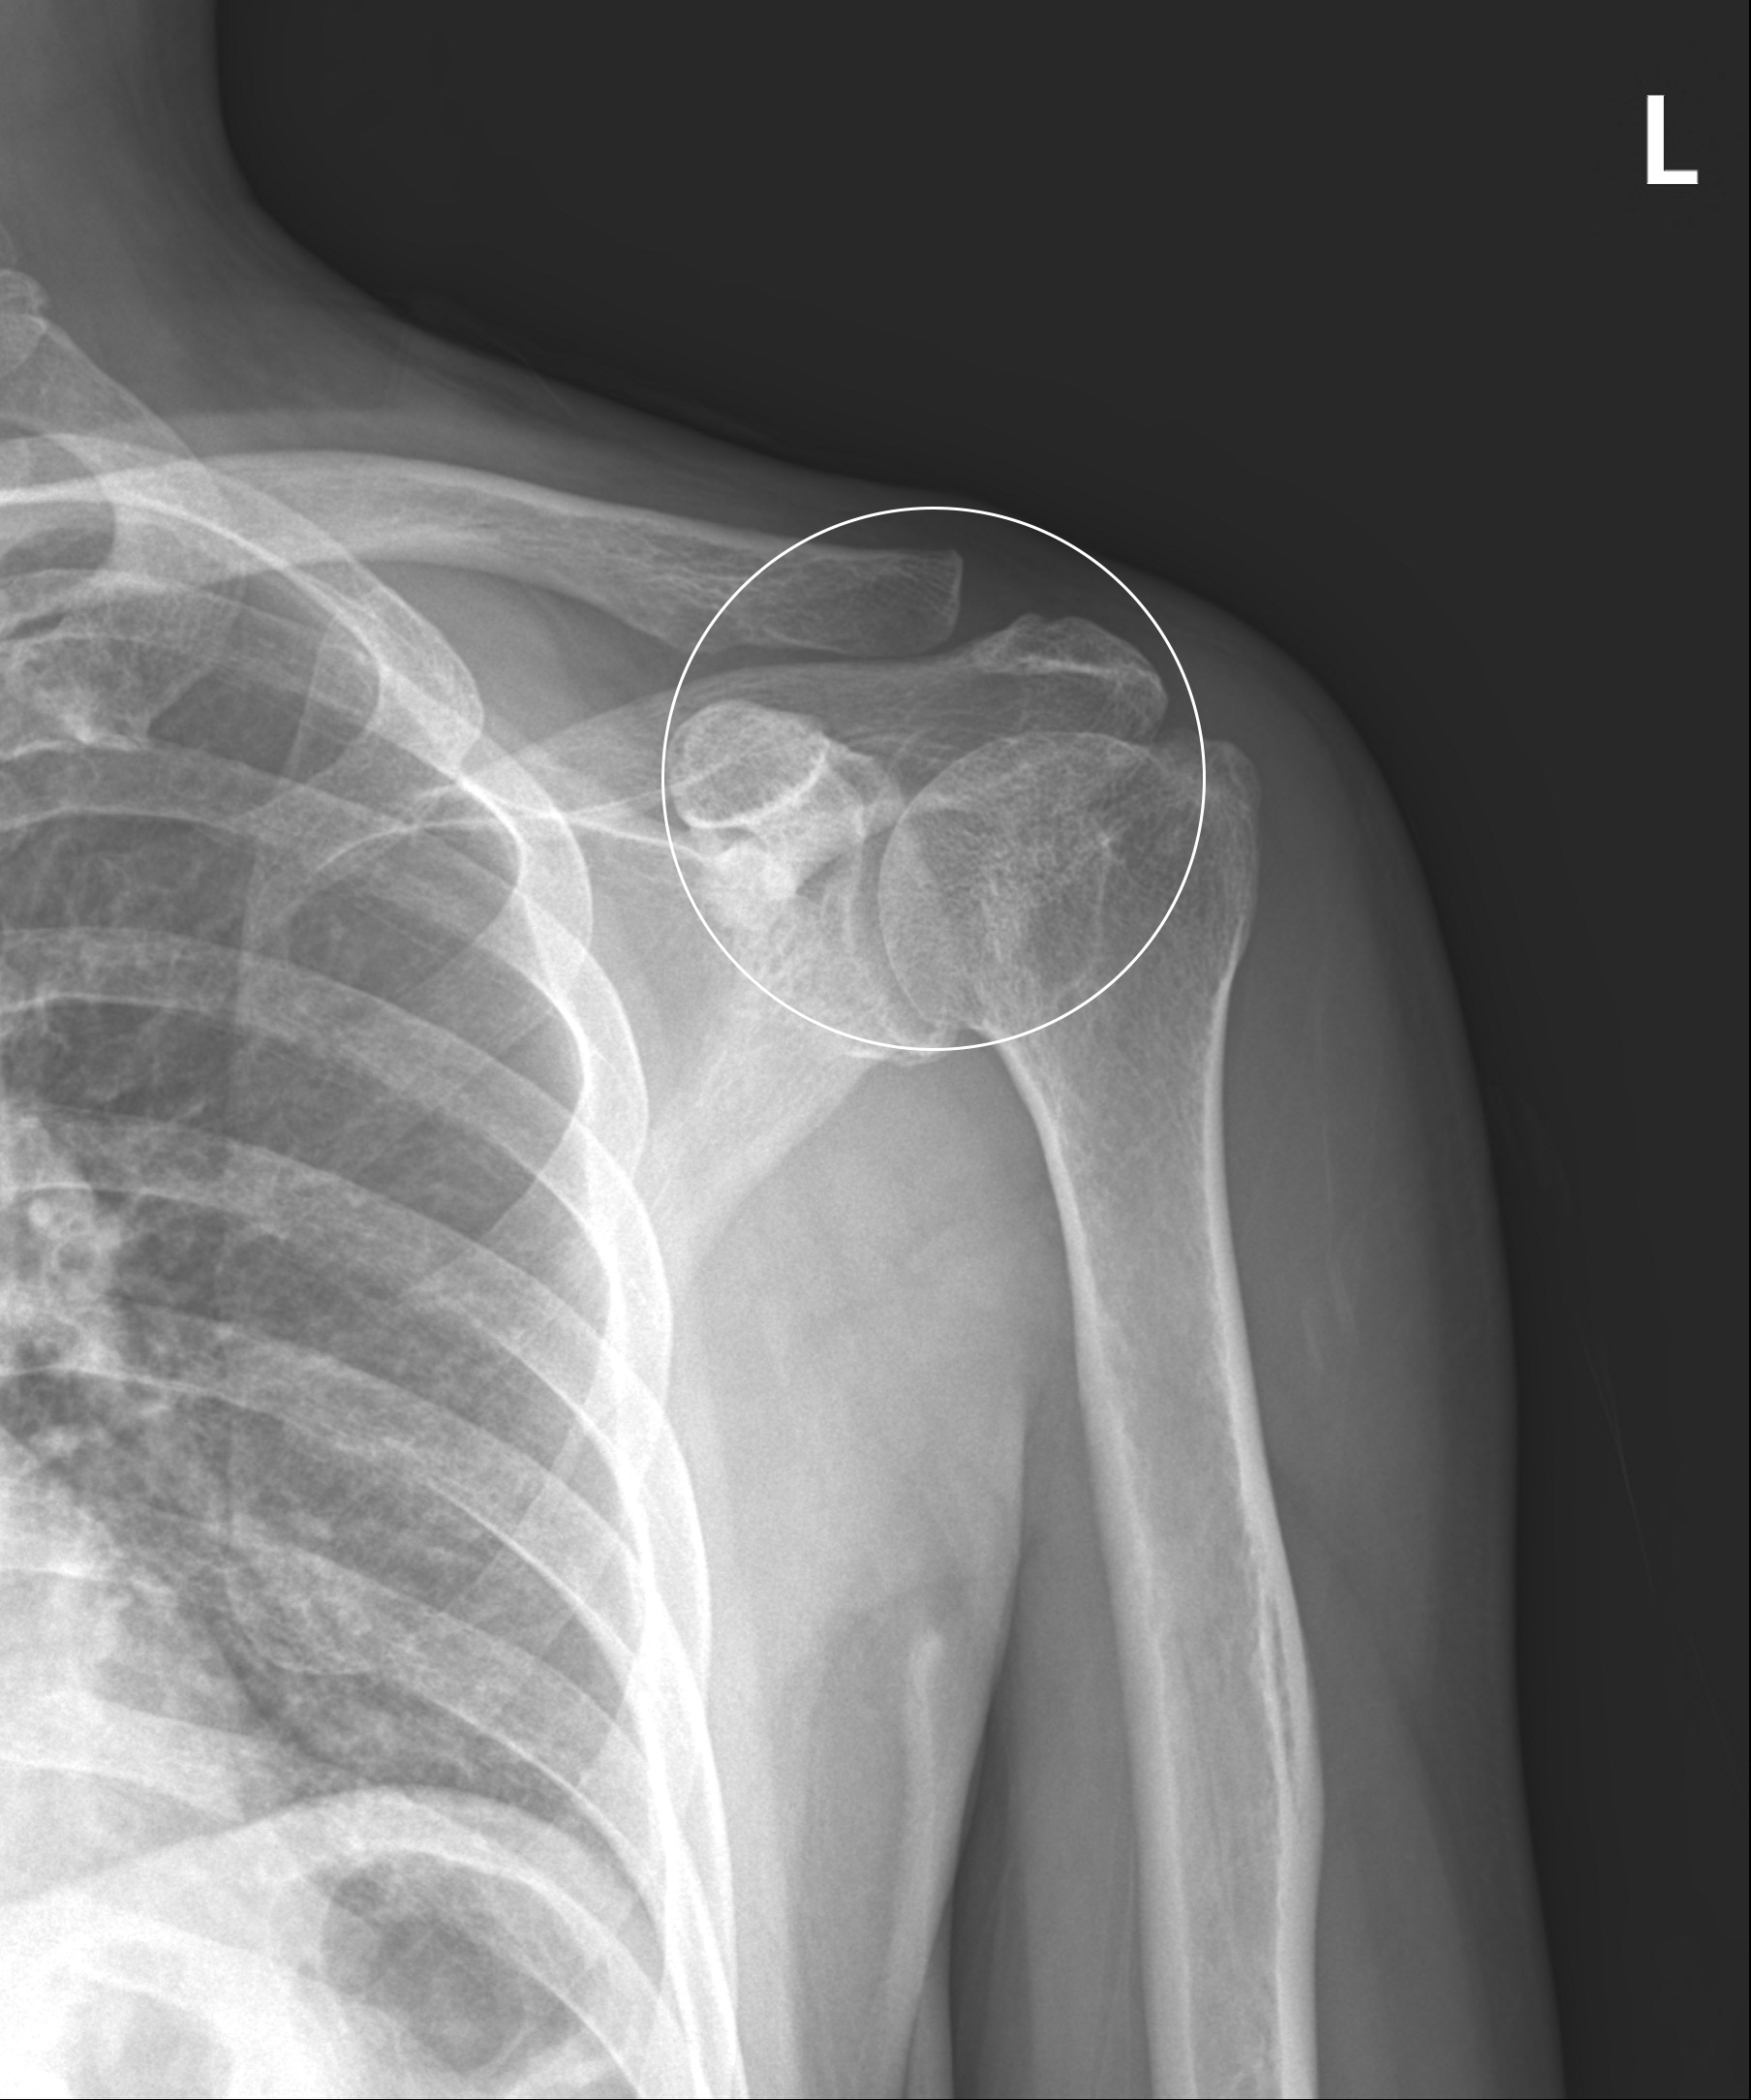

어깨충돌증후군

어깨 견봉과 위팔뼈인 대결절부 사이의 공간이 좁아지면서 뼈와 힘줄 사이에 마찰이 발생하는 질환을 말합니다. 정상 어깨관절에서는 이 공간이 충분하나 어깨를 많이 사용하거나 운동을 무리하게 한 경우 또는 퇴행성 변화 및 뼈의 변형으로 인해 견봉과 어깨 힘줄 사이에 간격이 줄어들어 마찰이 발생하고 힘줄 변성 및 통증이 발생하게 됩니다.

관절내시경을 이용한

견봉성형술 및 회전근개 변연절제술

2023-01-27

ㆍ환자 동의를 받은 자료이며, 이미지 사진은 실물과 다를 수 있습니다.